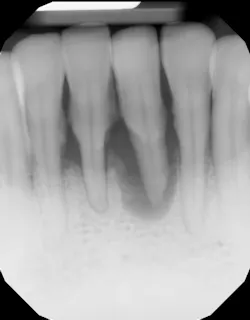

- Ensure tooth does not have a root fracture and check/refer for endodontic treatment if tooth is nonvital (figure 1)

- Proper surgical technique including incision, flap design, and complete detoxification of bony defect and root apices (figures 3 and 3a)